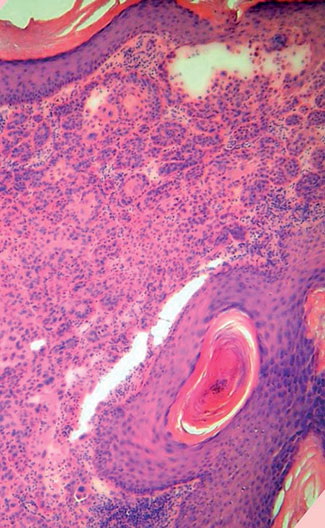

Squamous Cell Carcinoma = الكارسينوما شائكة الخلايا